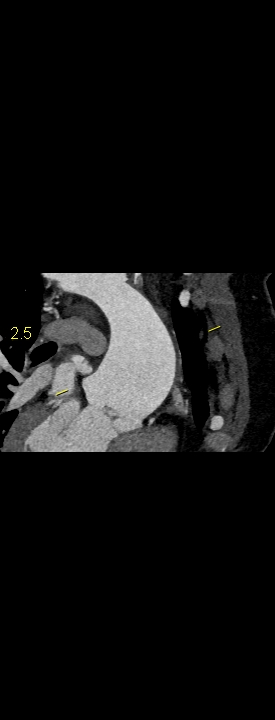

Figurile 1-5: reconstrucții multiplanare din achiziție angioCT aorta toracică

Discuţie caz nr 109: Pacient cu suspiciune de coarctaţie de aortă – are indicație de angioCT aortă toracică; medicul radiolog la acești pacienți este indicat să efectueze investigația cu sincronizare ECG deoarece coarctaţia de aortă poate fi asociată și cu bicuspidie de valvă aortică, mai ales că la acest pacient ecografia cardiacă descria creștere de calibru a aortei ascendențe. Pe reconstrucția cine în planul valvei aortice din achiziția cardioCT cu sincronizare ECG se remarcă o valvă aortică morfologic tricuspidă, funcțional bicuspidă ce asociază ectazie de aortă ascendentă și coarctaţie de aortă descendentă cvasicompletă cu dezvoltare de circulație colaterală intercostală și mamară internă.